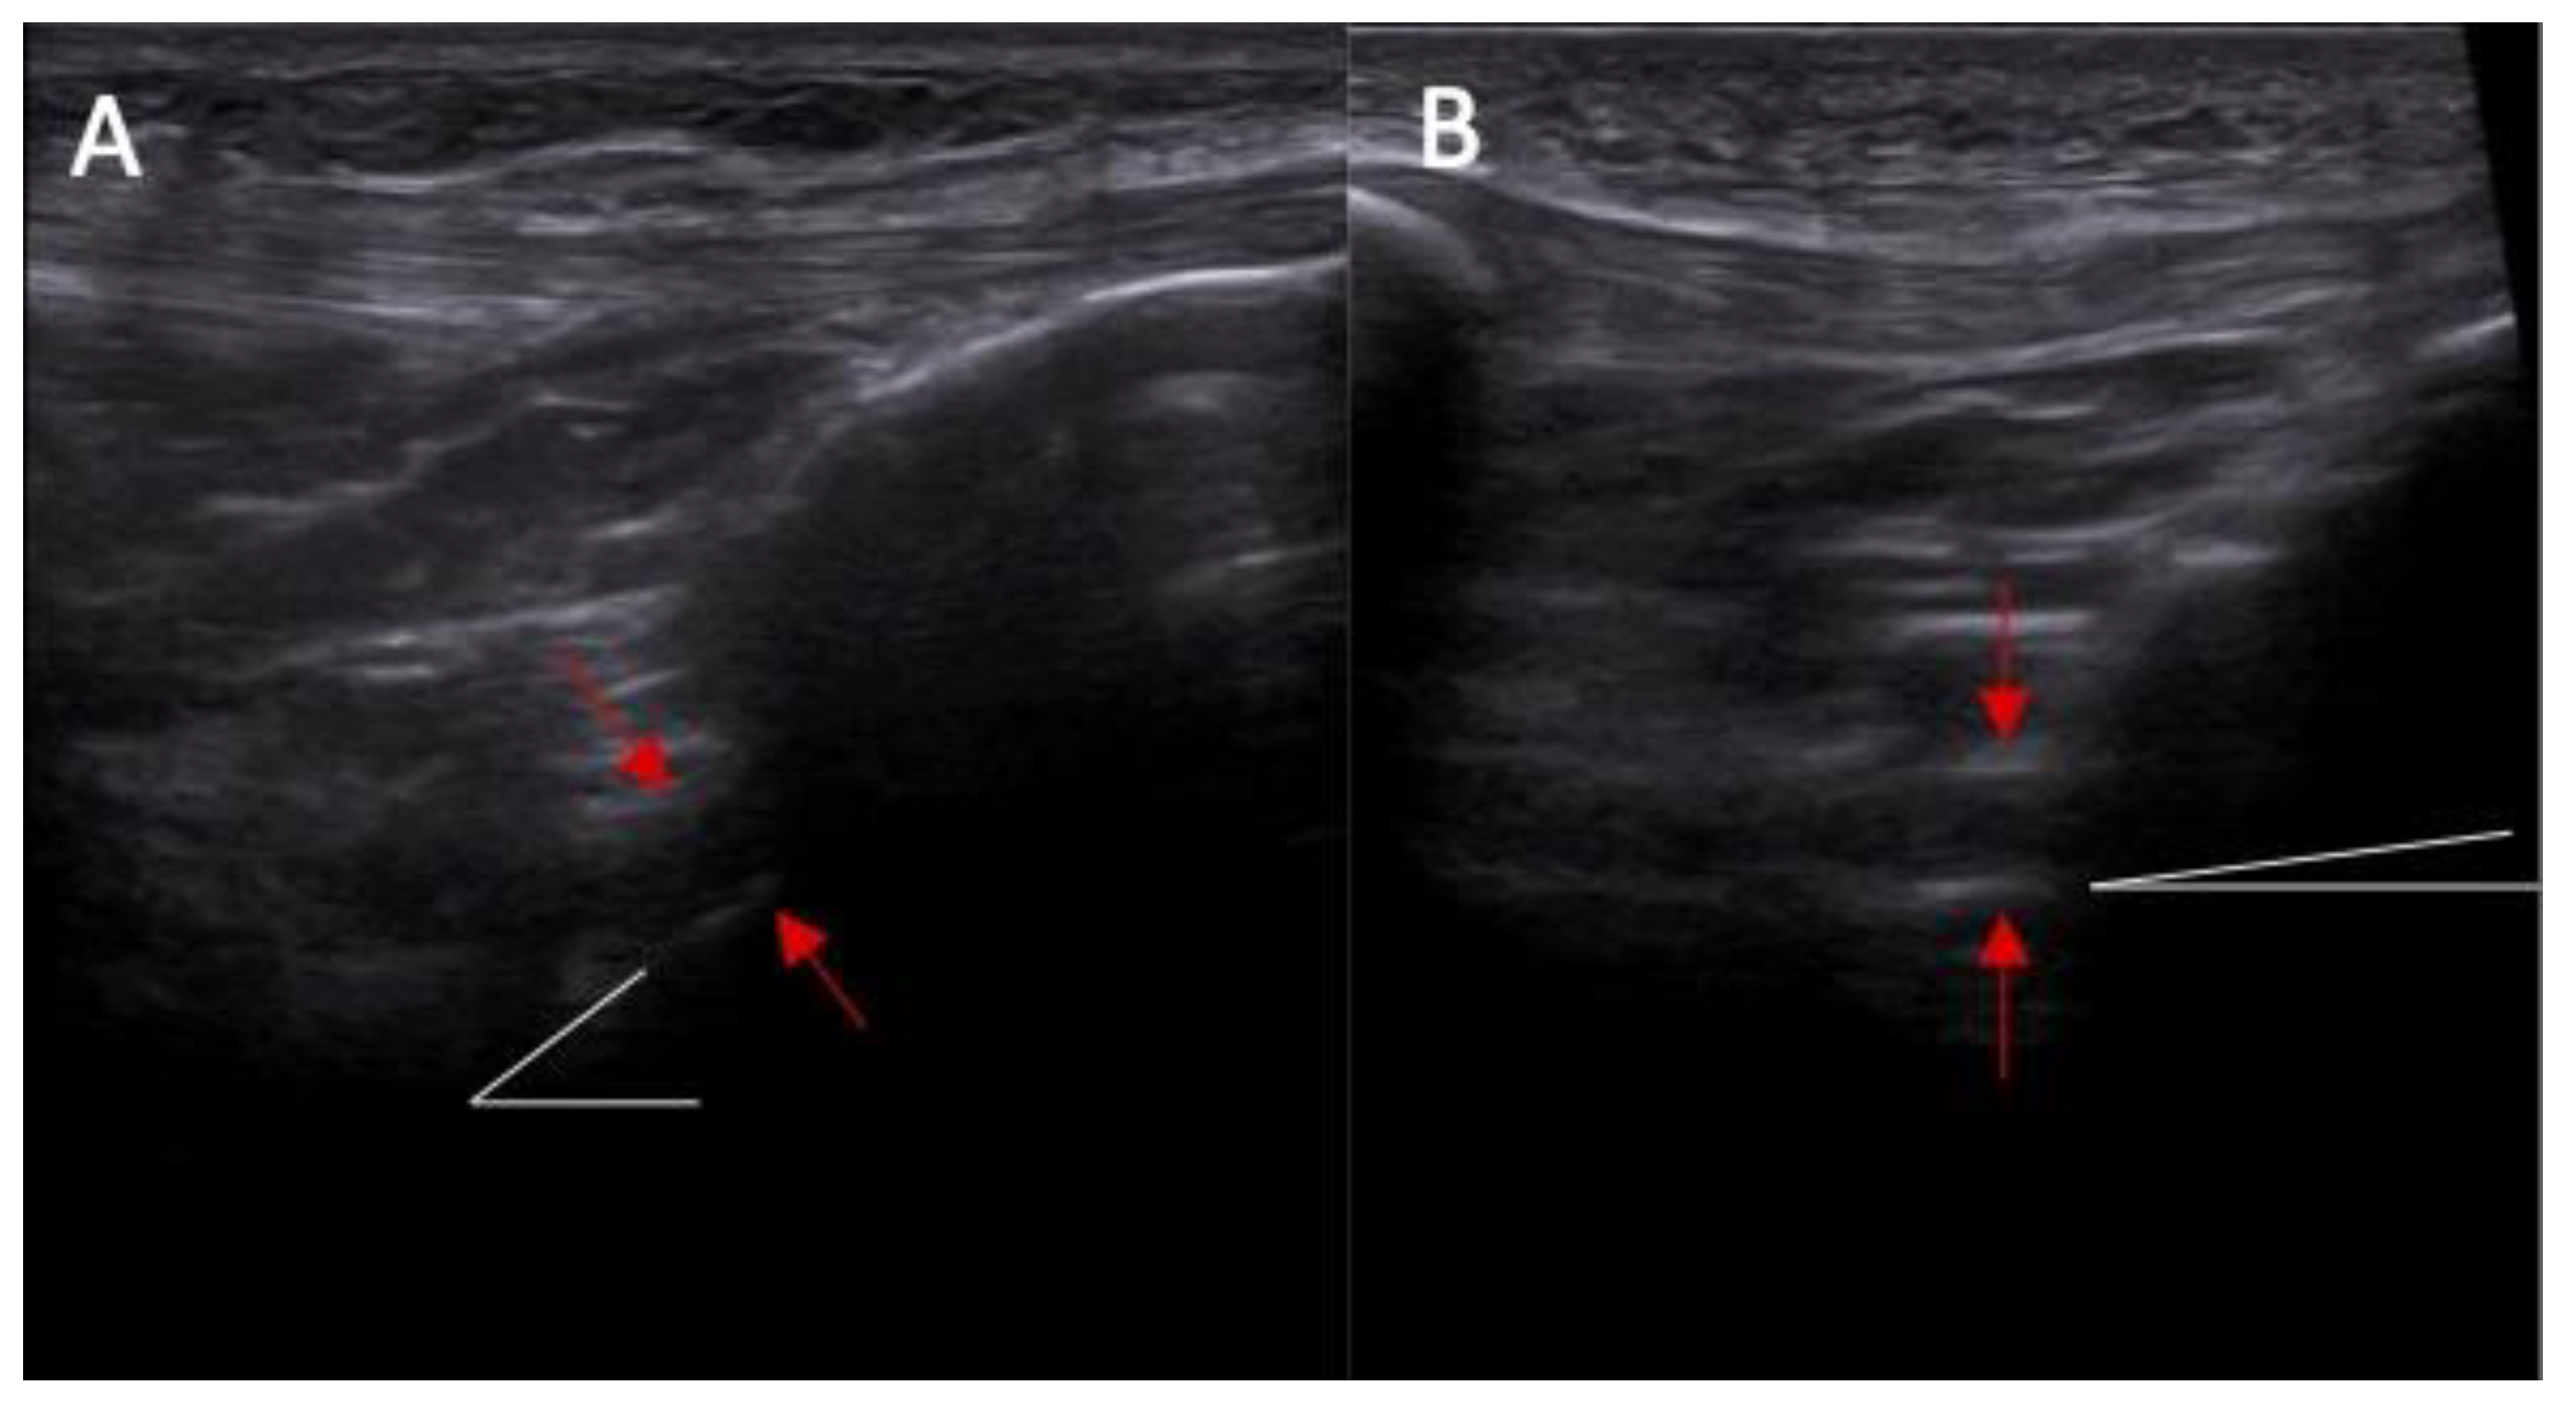

In all cases, in dynamic ultrasound examination after an ACL injury we reported instability. In all cases except one, we reported an abnormal inclination angle of the ACL. The sensitivity for instability and inclination angle in that part of the study was 100% and 90 %, respectively. Sample pictures of an anatomical study are presented in Figure 1 and Figure 2.

Anatomical part of the study. (A) Ultrasound examination: point A—baseline point of the ACL in the ultrasound image before the application of force and point B—the same point after the application of force in the anterior drawer test. Section A–B—actual functional instability on ultrasound examination. Yellow lines indicate the inclination of ACL. (B) arthroscopy view— arrows indicate intersection of the ACL.